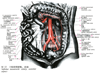

人体局所解剖図譜 IV巻